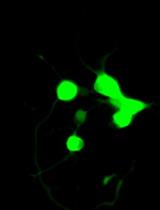

Interleukin-22 (IL-22) has been demonstrated as a critical regulator of epithelial homeostasis and repair; it showed an anti-inflammatory effect against ulcerative colitis. Local microinjection of IL-22 cDNA vector has been shown to be effective in treating ulcerative colitis in mouse models. However, microinjection comes with multiple technical challenges for routine colon-targeted drug delivery. In contrast, oral administration can get around these challenges and provide comparable efficacy. We showed in previous studies that oral administration of new lipid nanoparticles (nLNP)-encapsulated IL-22 mRNA targets the colon region and efficiently ameliorates colitis. This protocol describes the details of preparing and characterizing the nLNP-encapsulated IL-22 mRNA using three major lipids that mimic the natural ginger-derived nanoparticles. It provides an nLNP platform that can be used to orally deliver other types of nucleic acids to the colon.

We previously used ginger-derived lipid nanoparticles (GDNPs) for orally delivering CD98 siRNA (Zhang et al., 2017) and 6-shogaol (Yang et al., 2021) to treat ulcerative colitis. These studies suggested that GDNPs could overcome the challenges of oral drug delivery. Further, we found that monogalactosyl-diacylglycerol (MGDG), digalactosyl-diacylglycerol (DGDG), and phosphatidic acid (PA) constitute more than 90% of the total lipids of GDNPs (Zhang et al., 2016; Zhang et al., 2017). In this protocol, we will describe how to use these three lipids at the same ratios found in the GDNPs in the synthesis of new lipid nanoparticles (nLNPs) to encapsulate IL-22 mRNA. The nLNP-encapsulated mRNA showed its therapeutic efficacy in one of our recently published studies (Sung et al., 2022).